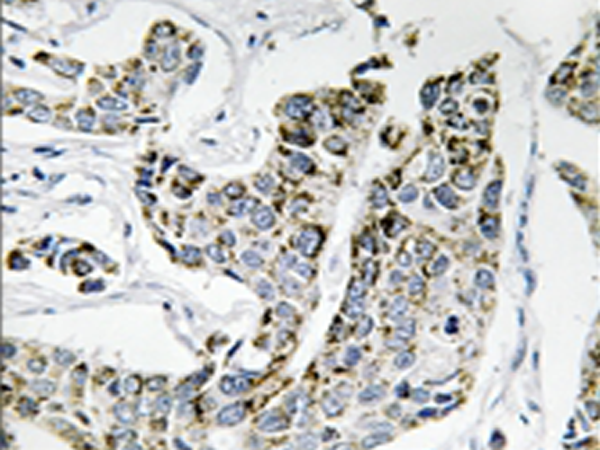

IHC positive control: |

Human breast carcinoma tissue |

IHC Recommend dilution: |

50-100 |